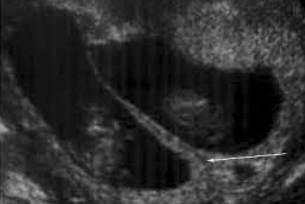

What is the diagnosis?

Dichorionic diamniotic twin gestation

Aka: Lambda or twin peak sign